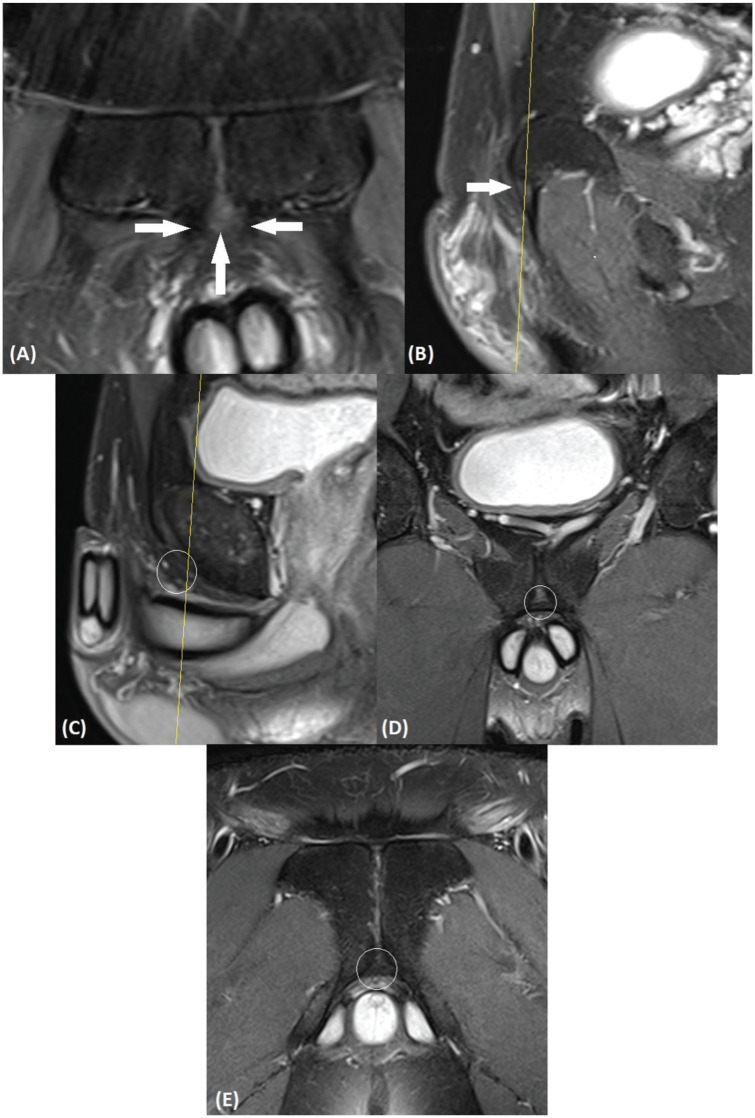

Abstract Image